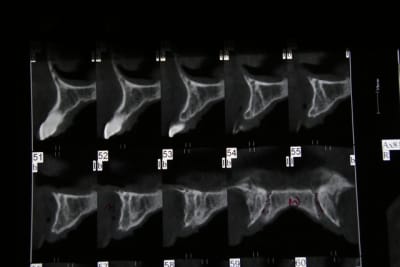

tes coupes, c'est tous les 1 ou 2 mm ?

tes latérales, elles ont des racines comment ? Sur le scan on a une image de racine résorbées

ce sont des coupes de 1mm , j'ai un peu moins de 10mm (sans compter le canal qui fait 2-3 mm de diam). Justement j'envisage d'enlever 22 (la moins fiable) et de poser implant 11-22 + bridge. Et si le patient refuse deux implants 11-21 mais les diam des implants vont vraiment etre faible .... no se